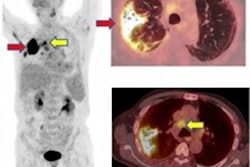

Another hot topic right now is PET/CT's role in tracking COVID-19 infection. At last week's Society of Nuclear Medicine and Molecular Imaging (SNMMI) annual meeting, a team from India elaborated on how F-18 FDG PET/CT can help to evaluate post-COVID lung disease. Find out more in our report from the congress.